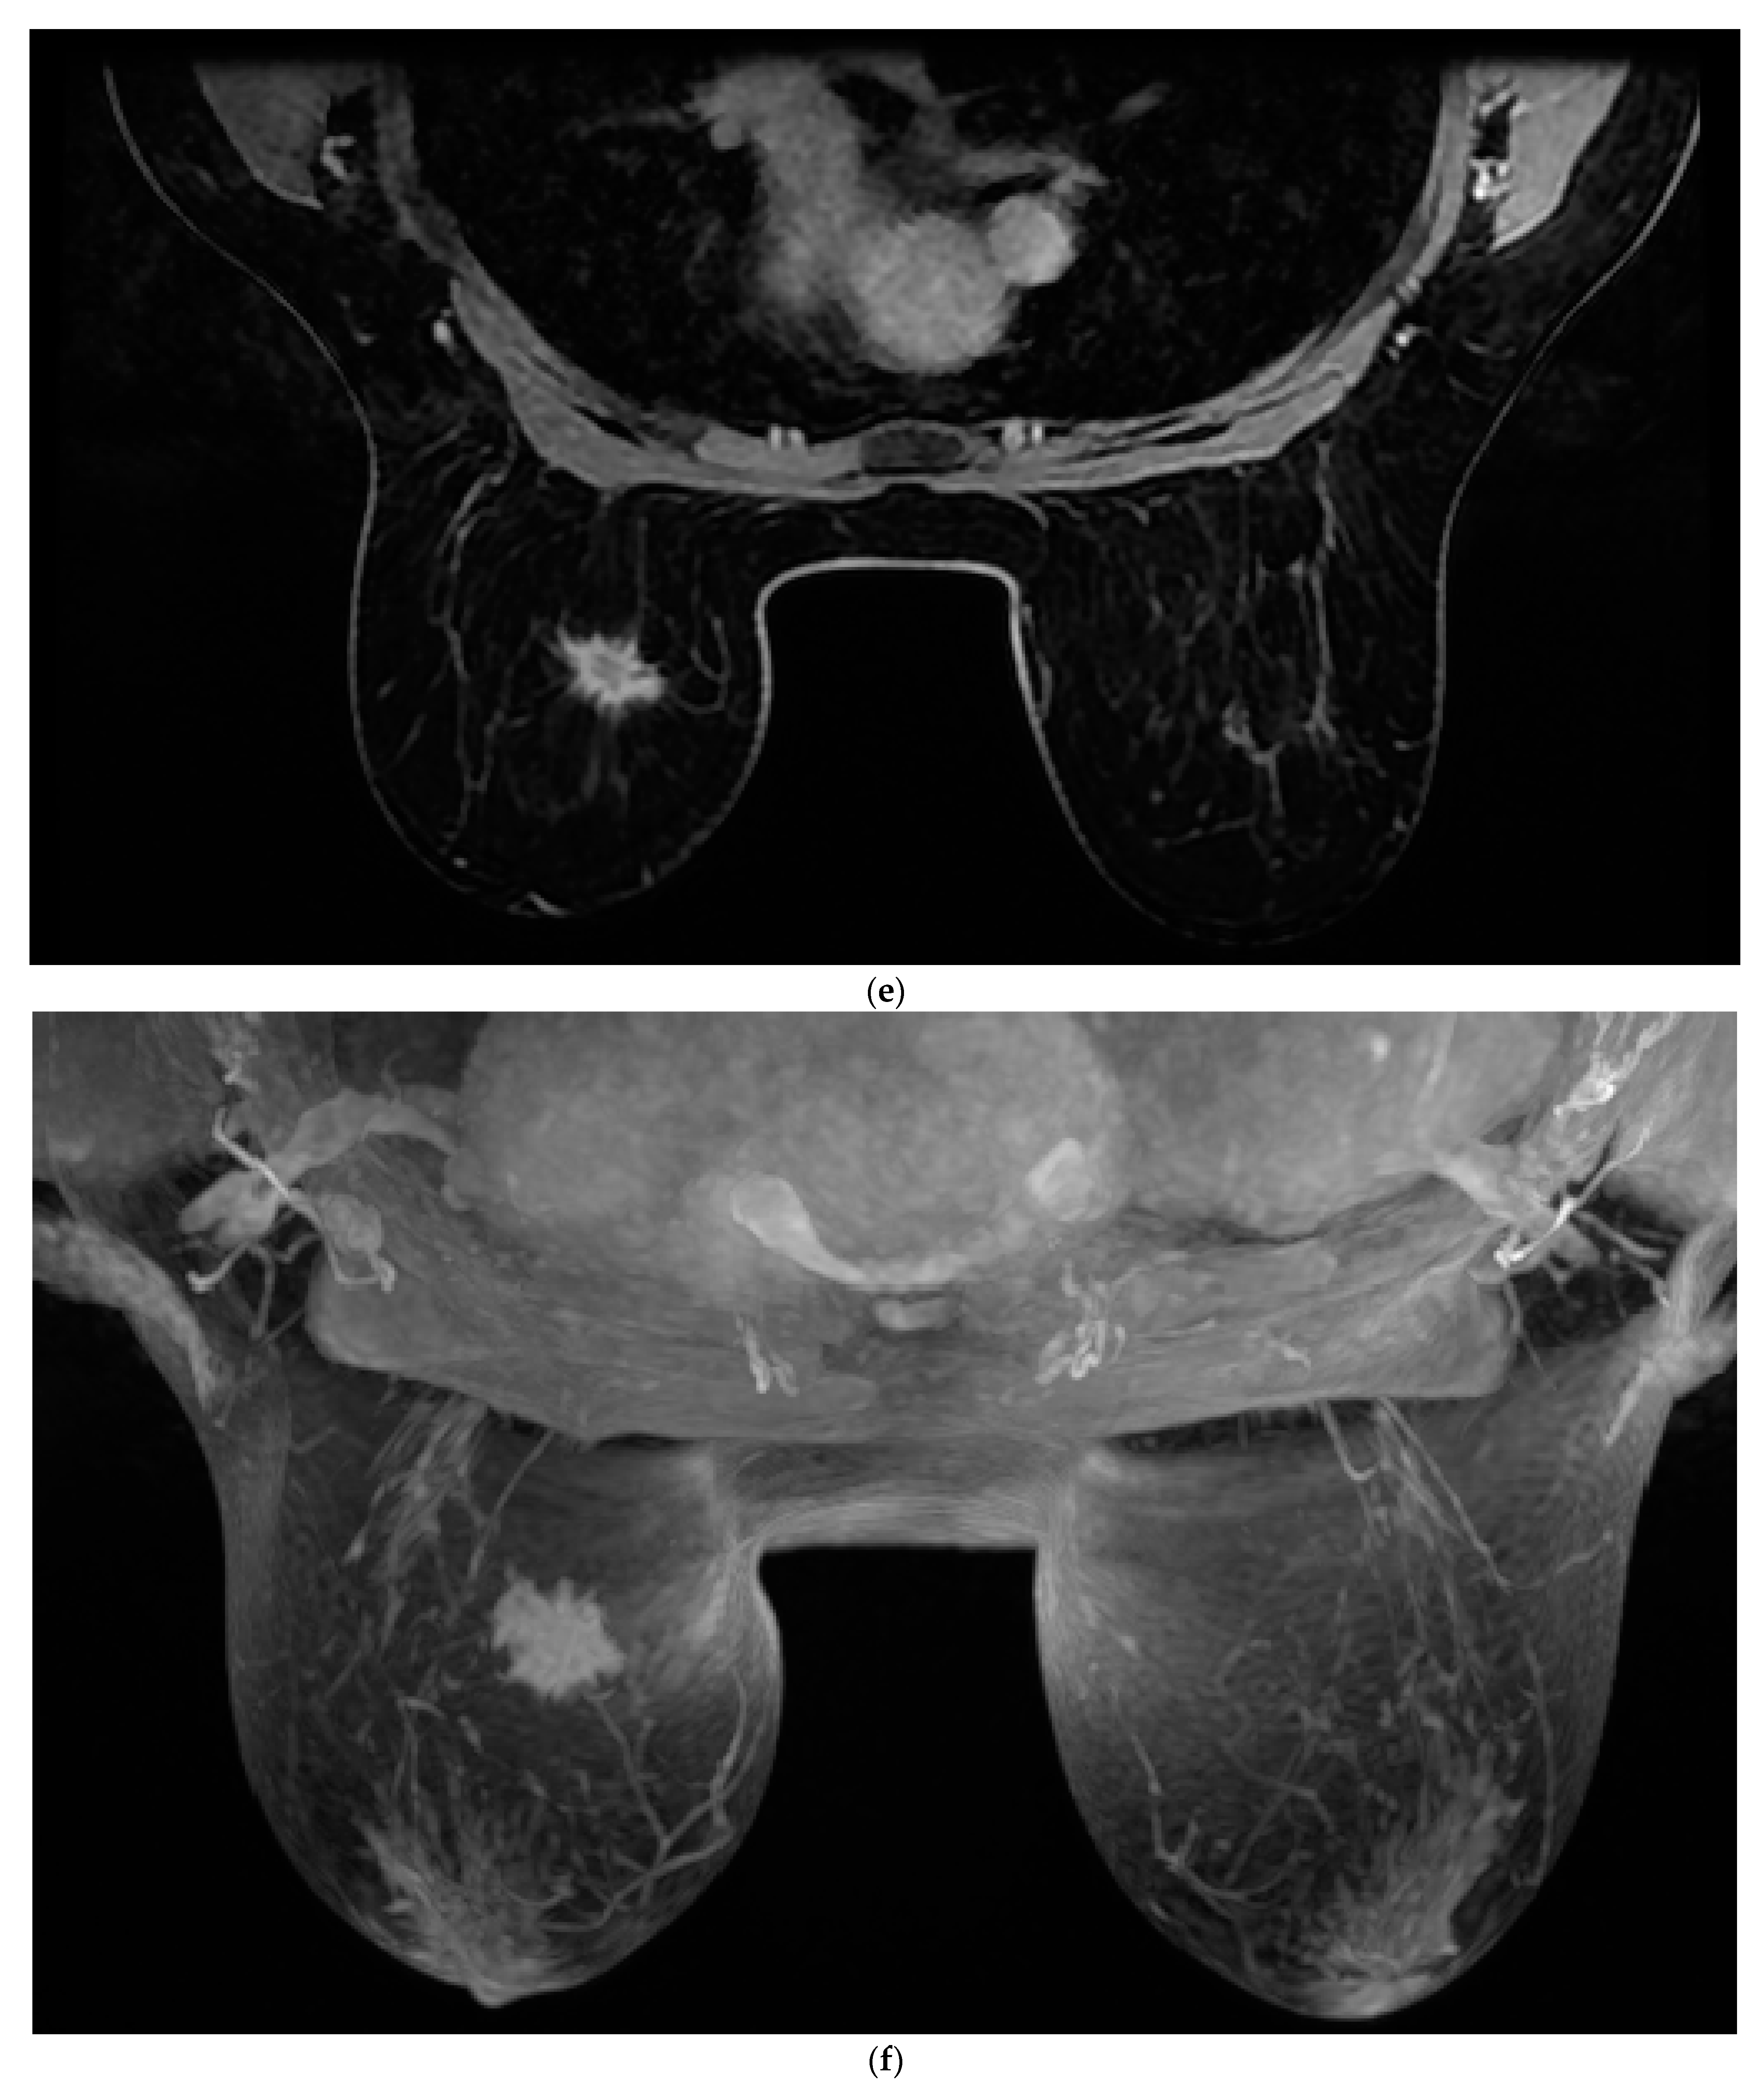

2.1. MRI and Analysis

Figure 1. Images of a 43-year-old woman with a new 2 cm left breast mass (invasive ductal carcinoma—IDC). (a) Native. (b) First postcontrast sequence. (c) Second postcontrast sequence. (d) Third postcontrast sequence. (e) Fourth postcontrast sequence. (f) Maximum intensity projection (MIP).